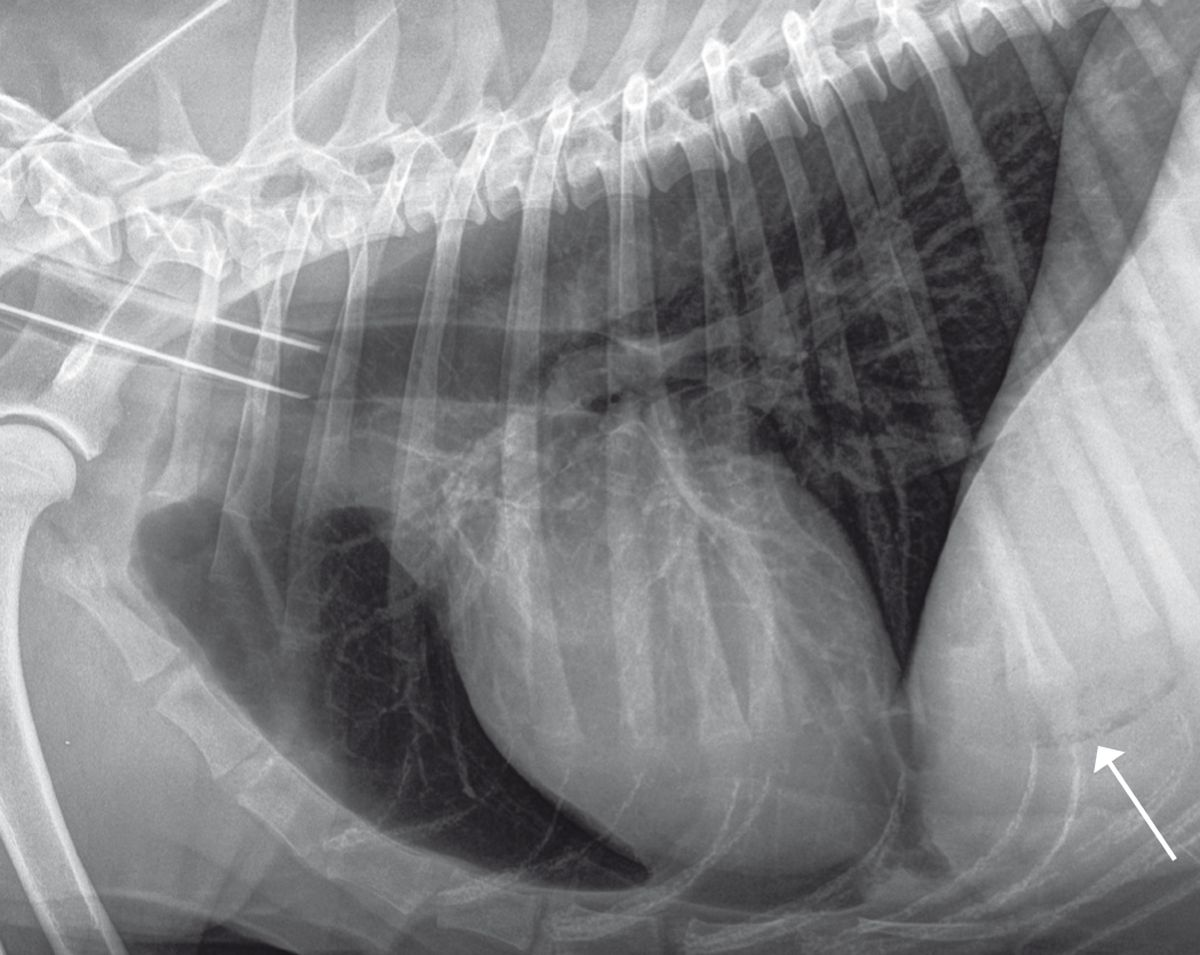

Radiografia poate contribui la evaluarea dimensiunii, formei, poziției, opacității și marginilor ficatului, precum și la detectarea prezenței gazelor sau a mineralizării (Figura 2). Ecografia contribuie la determinarea gradului de afectare hepatică (focală, multifocală sau difuză), precum și la evaluarea vascularizației și poate facilita prelevarea de probe (pentru citologie, cultură și biopsie) (Figura 3). Rețineți că absența modificărilor ecografice nu înseamnă neapărat că ficatul este sănătos.

Radiografie toracică laterală și abdominală anterioară a unui câine: există gaz în vezicabiliară (a se vedea săgeata) din cauza colangitei emfizematoase.

Figura 2. Radiografie toracică laterală și abdominală anterioară a unui cine: există gaz n vezicabiliară (a se vedea săgeata) din cauza colangitei emfizematoase. Jordi Puig